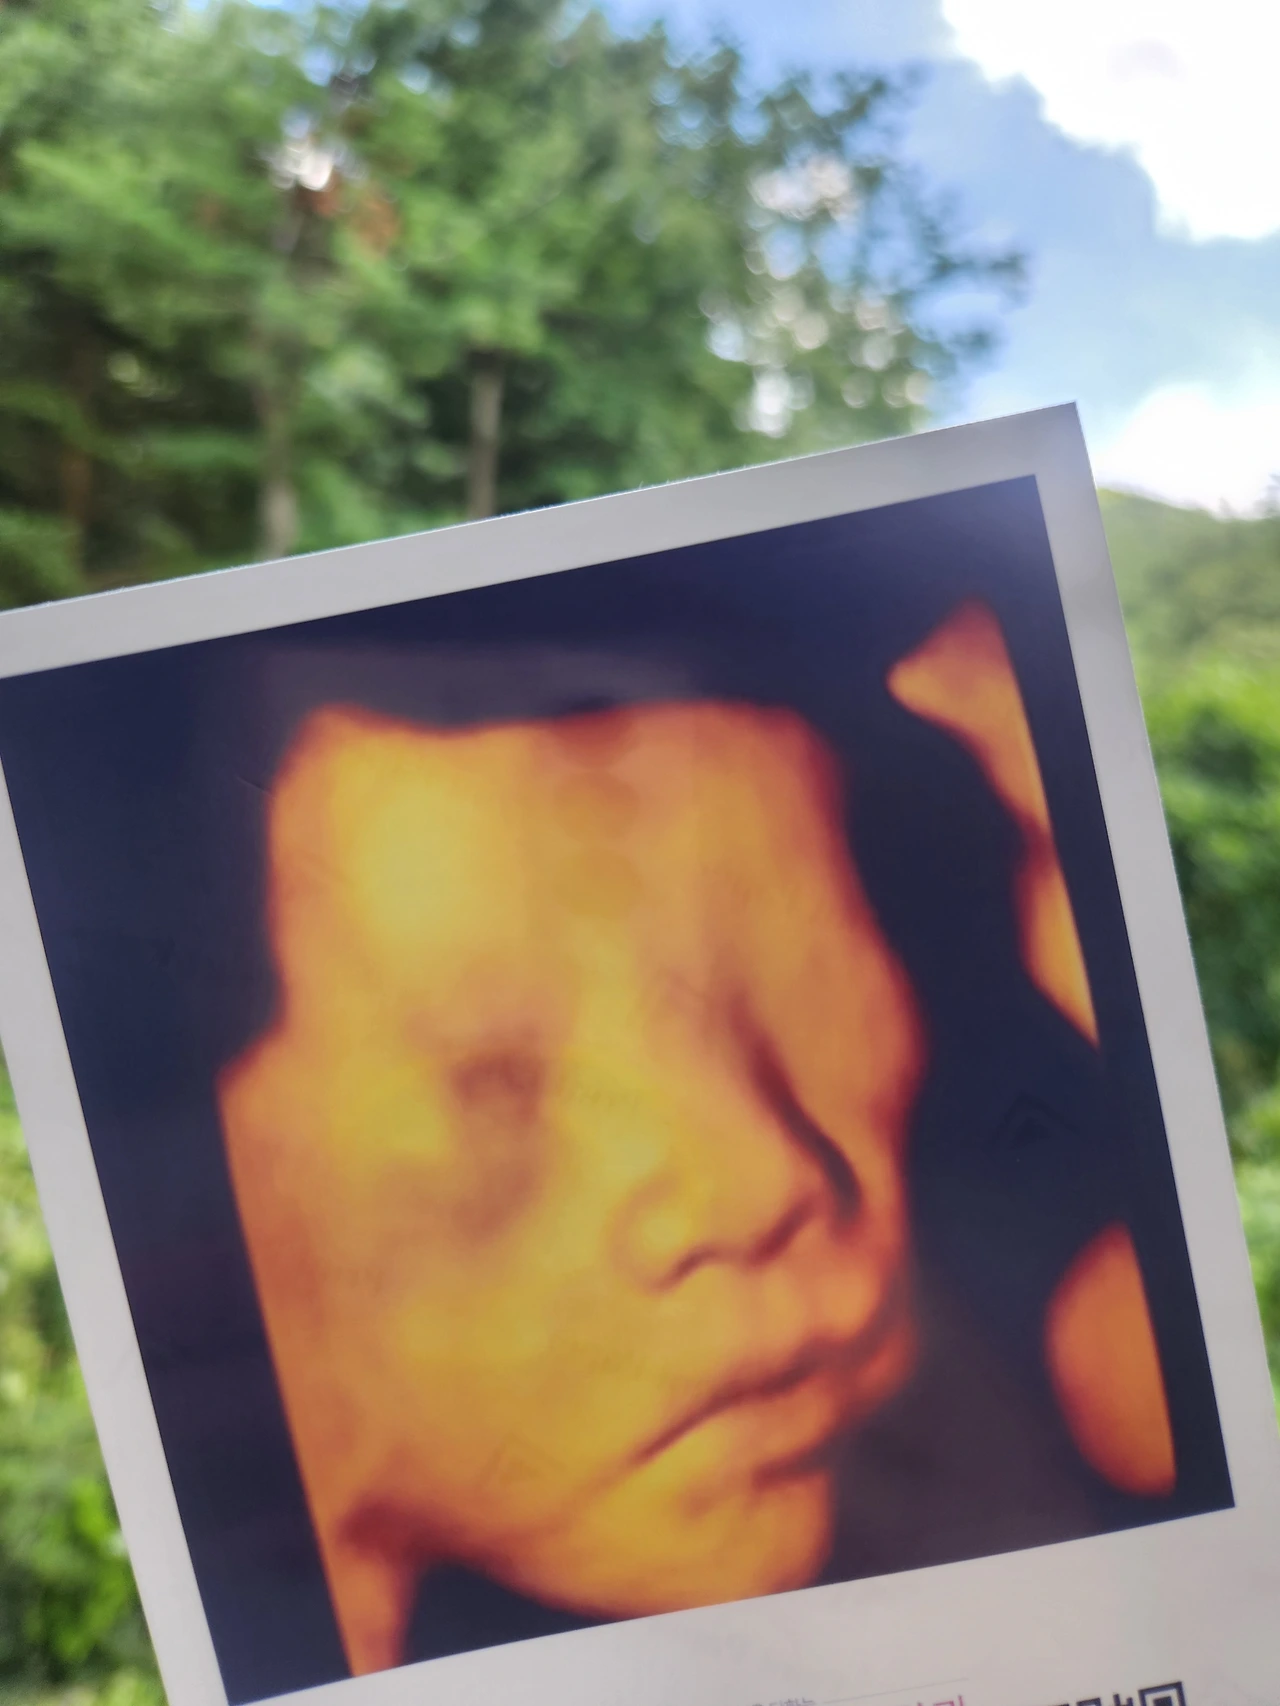

또 다른 기대는 아기와 함께 하게 될 시간이에요. 와, 아기라니. 아직도 믿기지가 않습니다. 나와 남편이 만나 생겨난 새로운 생명체라니. 내가 한 명의 사람을 키워내게 되다니.

이런 생각을 하면서 얻은 결론은 무엇보다 아기의 정서적 신체적 성장이 중요한 시기에 최대한 내가 함께 하겠다는 것입니다. 저에게도 아기에게도 생애 한 번뿐인 시기를 최대한 함께 보내고 싶은 마음이에요. 그래서 미리 남편과 육아 책도 함께 읽으며 공부하고 있습니다.